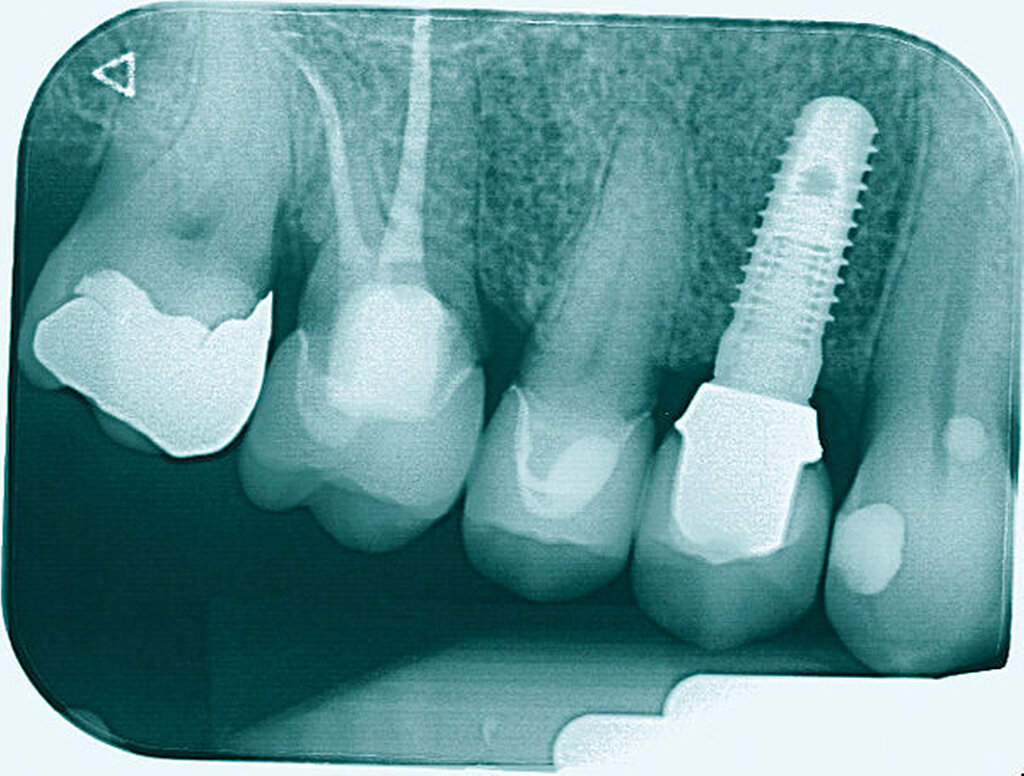

Eine 54-jährige Patientin stellte sich 2018 in der Praxis vor, nachdem sie beim Essen ein Goldinlay an Zahn 16 verloren hatte. Sie klagte über eine Aufbissempfindlichkeit des Zahnes sowie über das Gefühl einer Lockerung. Klinisch zeigte sich eine tiefe Fraktur des Zahnes in mesiodistaler Richtung. Nach klinischer und röntgenologischer Diagnostik wurde die Patientin über die Möglichkeit der Extraktion mit anschließender prothetischer Versorgung der Lücke und den aufwendigen Erhaltungsversuch mittels endodontischer Behandlung des Zahnes samt Amputation der palatinalen Wurzel aufgeklärt. Die Patientin war sehr motiviert und entschied sich für den Erhaltungsversuch.

So erfolgte nach endodontischer Behandlung des Zahnes die Amputation der palatinalen Wurzel und die Versorgung des Zahnes mit einer Vollkrone. Die Situation an 16 ist seitdem stabil, allerdings zeigen sich auch hier palatinal erhöhte Sondierungstiefen, die röntgenologisch mit einem progredienten Knochenabbau im Bereich der Furkation zu korrelieren scheinen. Die Patientin gibt an, mit der Reinigung des Zahnes keine Probleme zu haben, möglicherweise ist diese jedoch durch die Einziehung im Bereich der Furkation vor allem palatinal erschwert. Die Patientin wurde daraufhin instruiert, wie sie die häusliche Mundhygiene in den schwer zugänglichen Bereichen intensivieren und verbessern kann.

Eine 53-jährige Patientin stellte sich 2015 mit plötzlich aufgetretenen, starken Beschwerden an Zahn 16 und der Bitte um Abklärung vor. Es erfolgte die klinische und röntgenologische Befundung des Zahnes, der neben einer apikalen Parodontitis auch eine große, fast bis in die Furkation reichende Kronenrandkaries an der mesiobukkalen Wurzel aufwies. Um diesen vorhersagbar versorgen zu können, wurde der Patientin die endodontische Behandlung mit Amputation der mesiobukkalen Wurzel und anschließender Versorgung mittels Vollkrone als Alternative zur Extraktion aufgezeigt. Sie entschied sich für den Zahnerhalt.

So folgte nach der Wurzelfüllung die Amputation der mesiobukkalen Wurzel. Der Zahn wurde nach der Amputation auf Wunsch der Patientin zunächst mit einem Langzeitprovisorium versorgt, das im Verlauf gegen eine definitive Versorgung ausgewechselt wurde. Die Patientin ist seitdem an 16 beschwerdefrei, der Zahn ist stabil und hat eine gute Langzeitprognose.